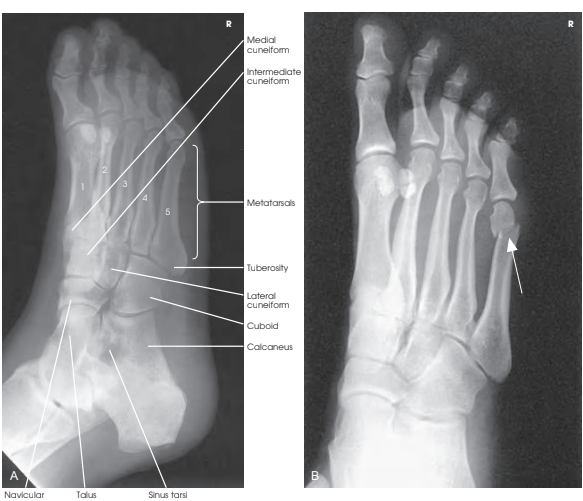

Structures shown (보이는 구조물)

| 내측 쐐기뼈 | Medial cuneiform |

| 중간 쐐기뼈 | Intermediate cuneiform |

| 외측 쐐기뼈 | Lateral cuneiform |

| 중족골 | Metatarsals |

| 결절 | Tuberosity |

| 입방뼈 | Cuboid |

| 발꿈치뼈 | Calcaneus |

| 발배뼈 | Navicular |

| 목말뼈 | Talus |

| 목말뼈 오목 | Sinus tarsi |

이미지에는 다음의 공간 및 구조물이 명확히 표시되어야 합니다:

- 입방골(cuboid)과 발꿈치뼈(calcaneus), 그리고 제4·제5 중족골

- 입방골과 외측 설상골 및 주상골(navicular bone)

- 외측 설상골은 옆모습으로, 종굴(sinus tarsi)은 잘 보이게 됩니다.

Evaluation criteria (평가 기준)

- 발가락부터 발꿈치까지 발 전체가 포함되어야 함.

- 발이 올바르게 회전된 상태:

- 제3~5 중족골은 서로 중첩되지 않음.

- 제1, 2 중족골 기저부는 내측 및 중간 설상골과 중첩됨.

- 나비뼈(navicular), 외측 설상골 및 입방골은 중첩이 적게 보임.

- 5번째 중족골 결절부(tuberosity) 명확히 보임.

- 외측 타르살중족골(TMT) 및 관절선 잘 나타남.

- 종굴(sinus tarsi) 명확히 보임.

- 연부 조직 및 골 소주구조 (Soft tissue and bony trabecular detail) 명확.